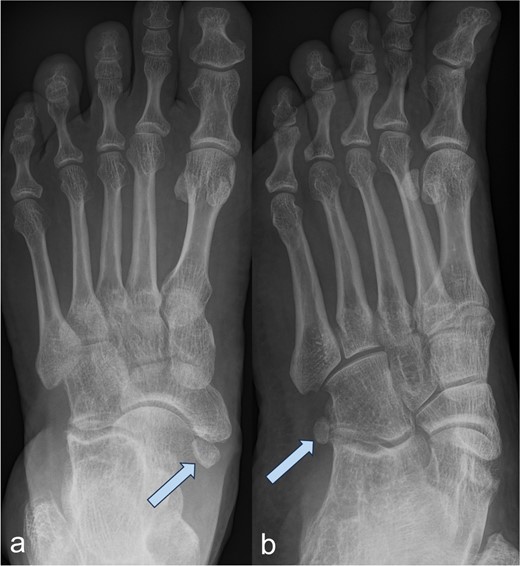

A 53-year-old man with a body mass index of 22.3 kg/m2 reported severe, load-dependent pain (6 out of 10 on the VAS) in the left foot, which had increased over the past two months. Light jogging as a recreational sport was no longer possible due to pain, and no trauma was recalled. Clinically, there was a mild pes planovalgus, with slight swelling and warmth medioplantarly and distal to the medial malleolus along the course of the tibialis posterior tendon. A marked point tenderness was noted, and forced dorsiflexion was severely painful. Conventional radiographs showed a triangular Type II Os tibiale externum at the typical site, measuring approximately 10.5 x 6 mm (Fig. 1a and b). Additional CT imaging in the axial plane with coronal reconstruction and subsequent 3D reconstruction (Fig. 2a and b) revealed a Type II Os tibiale externum with a distinct synchondrosis gap to the navicular bone. An MRI showed central inflammatory reaction in the synchondrosis and significant perifocal soft tissue edema of the Os tibiale externum with involvement of the tibialis posterior tendon, with no tendon rupture detected (Fig. 3a–d).

Image of an Os tibiale externum Type II in the anterior–posterior (a) and oblique (b) radiographic view; the ossicle is marked with an arrow.